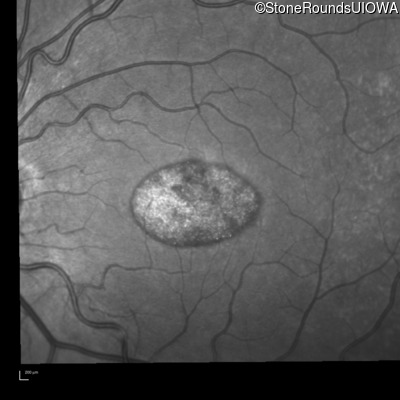

Infrared Fundus Photograph - Right - 20/20 -2 sc

Exemplar